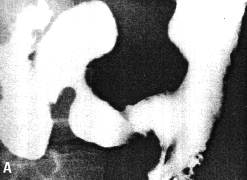

Case 33.12 E.L.J., 44 year old male. Radiology: 7.0 cm long constricting pyloric filling defect. Base of duodenal bulb normal (Fig. 33.12). Operation: large mass pyloric region with serosal spread. Duodenum appears normal. Widespread lymphatic metastases. Coeliac and para-aortic glands involved. Metastases in transverse mesocolon and spleen. Billroth II. Gastric histology: poorly differentiated adenocarcinoma (mucinous type with signet ring cells). Duodenal histology: spread into submucosa up to commencement of Brunner's glands. No infiltration of Brunner's glands or superficial mucosa.

![]() | |

| Fig. 33.12 A-D Case E.L.J. Constricting pyloric filling defect. Base of duodenal bulb normal. | |